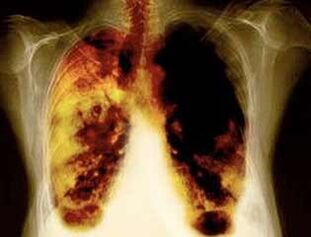

- Het verminderen van het risico op het ontwikkelen van longkanker en vele andere soorten kanker.

- Het verminderen van het risico op het ontwikkelen van bepaalde longziekten (bijvoorbeeld chronische obstructieve longziekte).

- In de periode van 2 weken tot 3 maanden na de afwijzing van roken verbetert het werk van de longen en wordt een toename van kracht gevoeld.

- Na 1-9 maanden vinden hoest en kortademigheid plaats: cilia (kleine haren) beginnen het slijm normaal te behandelen, de longen te reinigen en het risico op infectie te verminderen.

- 10 jaar na het stoppen van roken met 40%daalt de kans op longkanker met 40%.